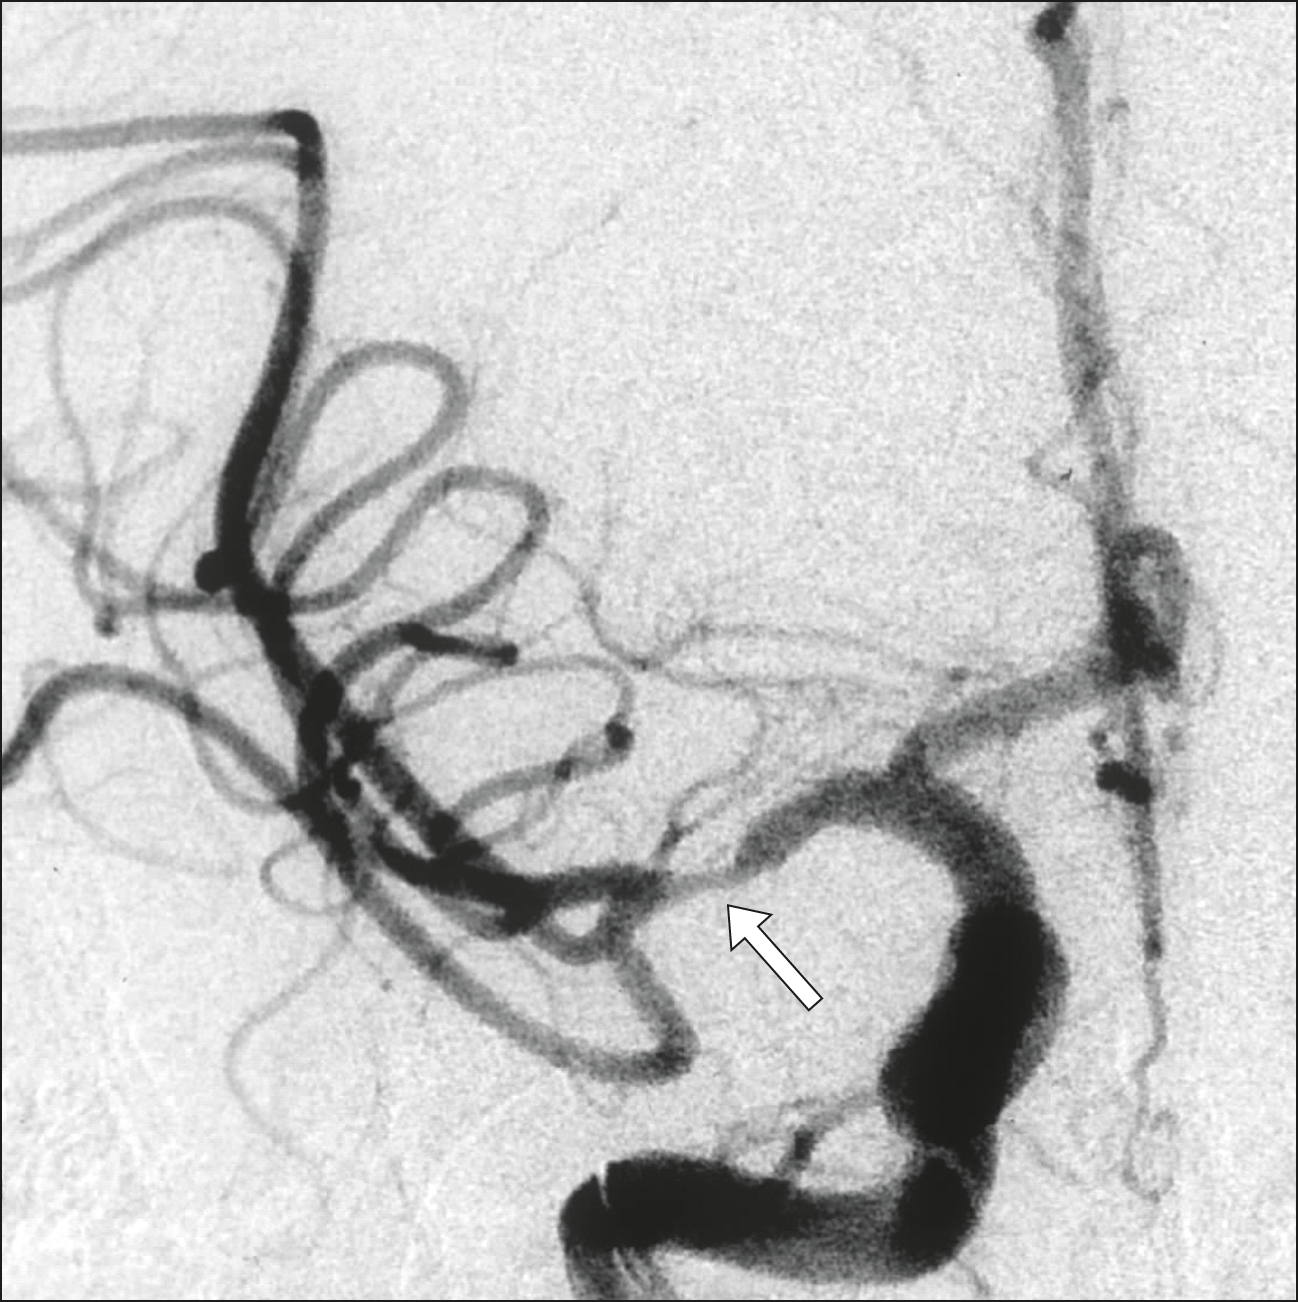

Tratamiento endovascular del ACV isquémico agudo de territorio anterior

La experiencia de un centro especializado de la Ciudad de Buenos Aires muestra que el tratamiento de urgencia para la reperfusión del ACV isquémico de territorio anterior puede alcanzar resultados compatibles con los estándares internacionales. Medicina (Buenos Aires), mayo de 2020.

El registro nacional holandés de las intervenciones para el tratamiento inicial del ACV isquémico muestra resultados comparables a los obtenidos en los ensayos clínicos. BMJ, marzo de 2018